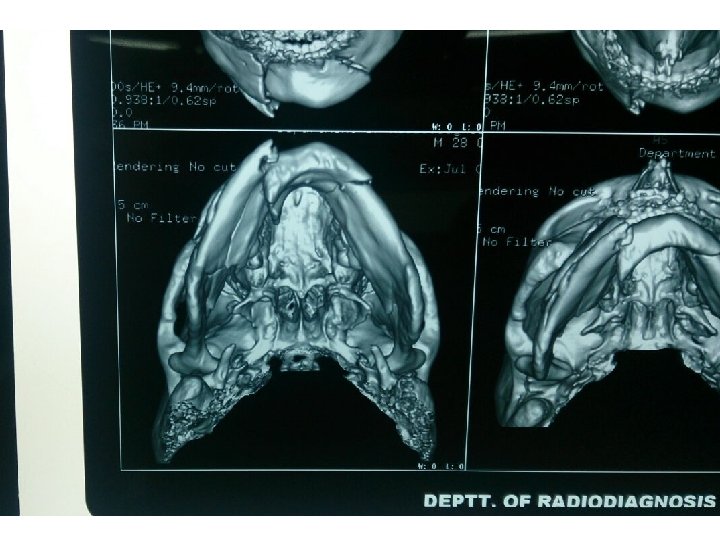

Edentulous mandible fracture Scan

Body& Angle fract Comminut ed # Gunshot inj. Axe/shrp obj

Area of weakness-Vulnerable to Fracture Junction of alv bone and basal mnd bone-so DA # are independent to mandibular fracture. Symphyseal #-formed by the union of two half of mandible in centre at irst year of life. So area of weakness. Parasymphyseal region- lateral to the mental prominence-presence of mental formen. Body region-junction of thicker body with Ramus-angle regionand due to curvature of trajectories in this region.

Anatomical variations Strength of lower jaw varies with presence r absence of tooth. Presence of impacted tooth r long root of cannine make the area vulnerable for fracture. Condylar region-slender neck of condyle render to fracture as a result of direct violence to chin. acts as safety mechanism to prevent injury to middle cranial fossa. Curve of mandible is more distorted from trauma-so buccal and lingual plate fractures at different level-this may give appearance of double fracture.